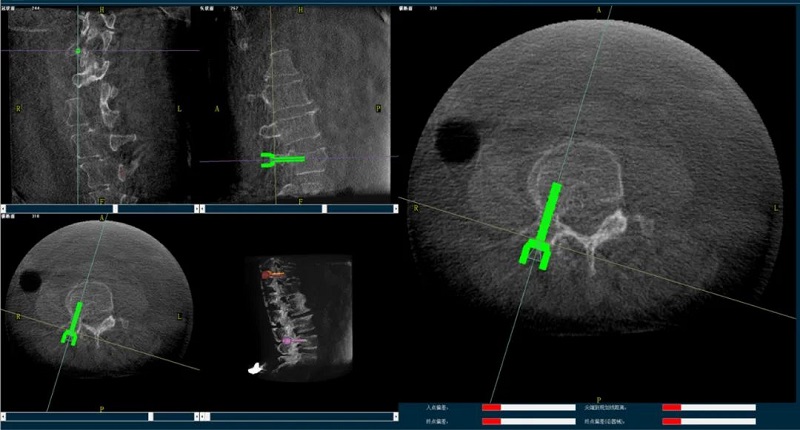

机器人辅助下椎体成形术,是以手术机器人智能机械臂为基础,仿照经皮骨水泥椎体成形术的施术步骤,限定穿刺点、穿刺方向、角度和深度,使穿刺针经过安全路径进入目标区域,然后进行骨水泥注入,辅助手术设计、精准指导手术实施。以普爱医疗的骨科手术机器人PL300B为例,其辅助进行的一例胸腰椎压缩性骨折经皮椎体成形术的过程如下:

(2)医生制定个性化的手术方案,在机器人导航界面上进行路径规划;